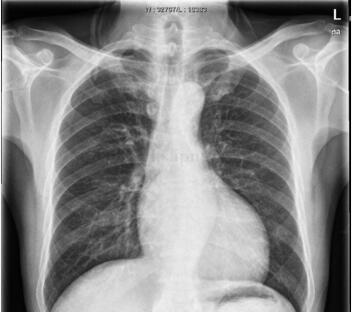

图3‐19‐3 入院当时查胸片提示心影明显增大

心脏彩超:LVDd77mm,LAD48mm,EF27%,左心房、左心室明显扩大,左心室室壁运动幅度明显普遍减低,左心室收缩功能明显减低。

急诊收入ICU,呼吸机无创辅助呼吸,监测心电、血压、呼吸、脉搏氧饱和度。纠正酸中毒、平喘、解痉、抗炎及其他对症支持治疗,患者症状有所缓解。追问病史,患者既往有30年饮酒史,每日饮白酒250g,已戒酒,但发病前又有饮酒史。会诊后诊断为酒精性心肌病、心功能不全转入CCU,予抗凝、抗血小板、减少心肌耗氧、改善心力衰竭、减轻心脏负荷、抑制胃酸分泌、保护胃黏膜等治疗。病情平稳后查心脏彩超提示左心房、左心室明显扩大,LVDd77mm,LAD48mm,左心室室壁运动幅度明显普遍减低,左心室收缩功能明显减低,EF27%。经治疗患者症状明显缓解,可在病房平地步行,无胸闷、胸痛,无心悸、气促。复查肌钙蛋白0.48ng/ml,CK44U/L,CK‐MB42.5U/L。予办理出院,嘱其注意继续服药,门诊随访。5个月后复查心脏彩超示各心腔大小及心内结构未见异常,EF59%;左心室舒张功能减退,收缩功能正常。

患者,老年男性,因突发呼吸困难5小时,加重2小时入院。有吸烟史30年,每日约30支,饮酒30年,每日约饮250g白酒。既往心脏彩超提示左心室、左心房大,左心室弥漫性运动减弱。患者有长期饮酒史,心电图提示心腔扩大,且有左心室肥厚表现,发病前戒酒半年余,本次发病前曾有饮酒史,心脏扩大考虑酒精性心肌病,NT‐proBNP>3000pg/ml,本次急性发病考虑系急性肺水肿、心源性哮喘。患者无典型心绞痛表现,但肌钙蛋白、心肌酶谱升高,考虑与心功能不全心肌损害有关。入院后控制急性心力衰竭后予美托洛尔,维持剂量为95mg,每日1次口服,坚持随访,监督患者戒酒,5个月后复查心脏彩超心功能及心脏大小均正常。